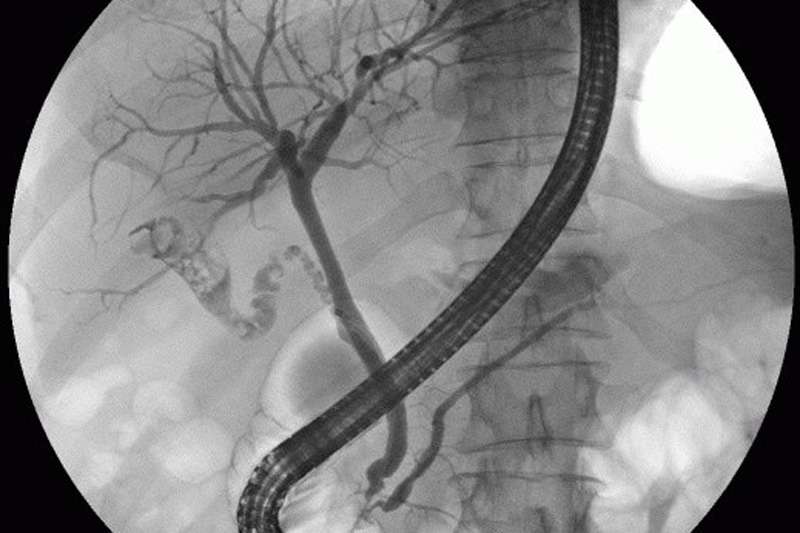

Awesome Image Awesome Image